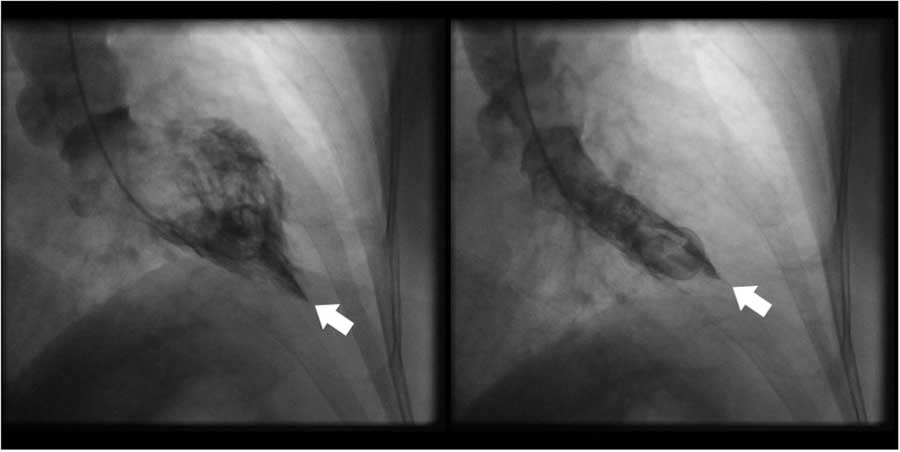

The patient was treated for an acute ST-elevation myocardial infarction (STEMI) in the ED and was later admitted to the coronary care unit (CCU) after the initial treatment. He was initiated on aspirin, clopidogrel, intravenous heparin infusion, and atorvastatin. As the patient presented to a non–percutaneous coronary intervention (PCI) capable hospital, the anticipated first medical contact to device time was >120 minutes; tenecteplase 50 mg was administered intravenously 60 minutes into his presentation. The patient was free of chest discomfort 90 minutes into admission. During admission, serial ECGs showed no resolution of the ST-segment elevation and persistent T-wave inversion (Figure 1). High-sensitivity cardiac troponin T was within normal limits, and both troponin and creatine kinase remained stable over several days. A coronary angiogram performed 13 hours into his presentation revealed normal coronary arteries without evidence of obstructive coronary disease with a left ventriculography demonstrating obliteration of the apical cavity at end-systole (Figure 2). Transthoracic echocardiography revealed a progressive increase in LV wall thickness toward the apex without evidence of LV systolic dysfunction or outflow tract obstruction (Figure 3). However, apical views were suboptimal, and no spade-like appearance of the apex was observed. On admission day three, the patient was discharged home on metoprolol.

Figure 2 Left ventriculogram in right anterior oblique orientation showing (a) end-diastolic ace-of-spades configuration and (b) end-systolic obliteration of the apical cavity. White arrow indicates cardiac apex.